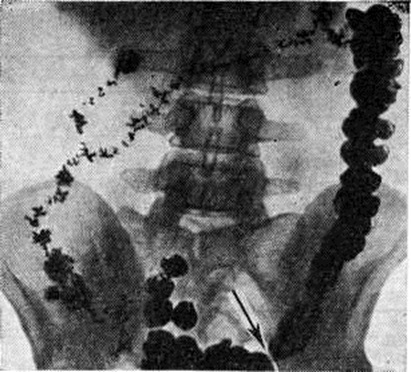

Рис. 1.

Рентгенограмма толстой кишки при первичном запоре (колит) через 48 часов после приёма бария внутрь: стаз контрастной массы преимущественно в левой половине кишки, тонус неравномерно повышен, гаустрация усилена, спастическая перетяжка в области сигмовидной кишки (указана стрелкой).

При первичных Запоры обычно обнаруживают снижение моторной функции, повышение, или понижение тонуса кишки. Эти изменения могут распространяться на всю кишку или на отдельные её сегменты (рисунок 1). Рельеф слизистой оболочки имеет нормальный или несколько «раздражённый» характер (ирритационный рельеф): складки приподняты, расположены более продольно или поперечно, но лишены, признаков воспаления. Смещаемость кишки не нарушена. При гиперкинетических Запоры замедление пассажа бария сочетается с регионарным спазмом и глубокой, нередко сегментирующей гаустрацией в виде многочисленных перетяжек (рисунок 2). Спазмированный отдел кишки иногда имеет вид тонкого шнура (рисунок 3). Реже, при атонических Запоры, обнаруживают пониженный тонус всей толстой кишки или отдельных её сегментов, сопровождающийся расширением просвета, поверхностной сглаженной гаустрацией.